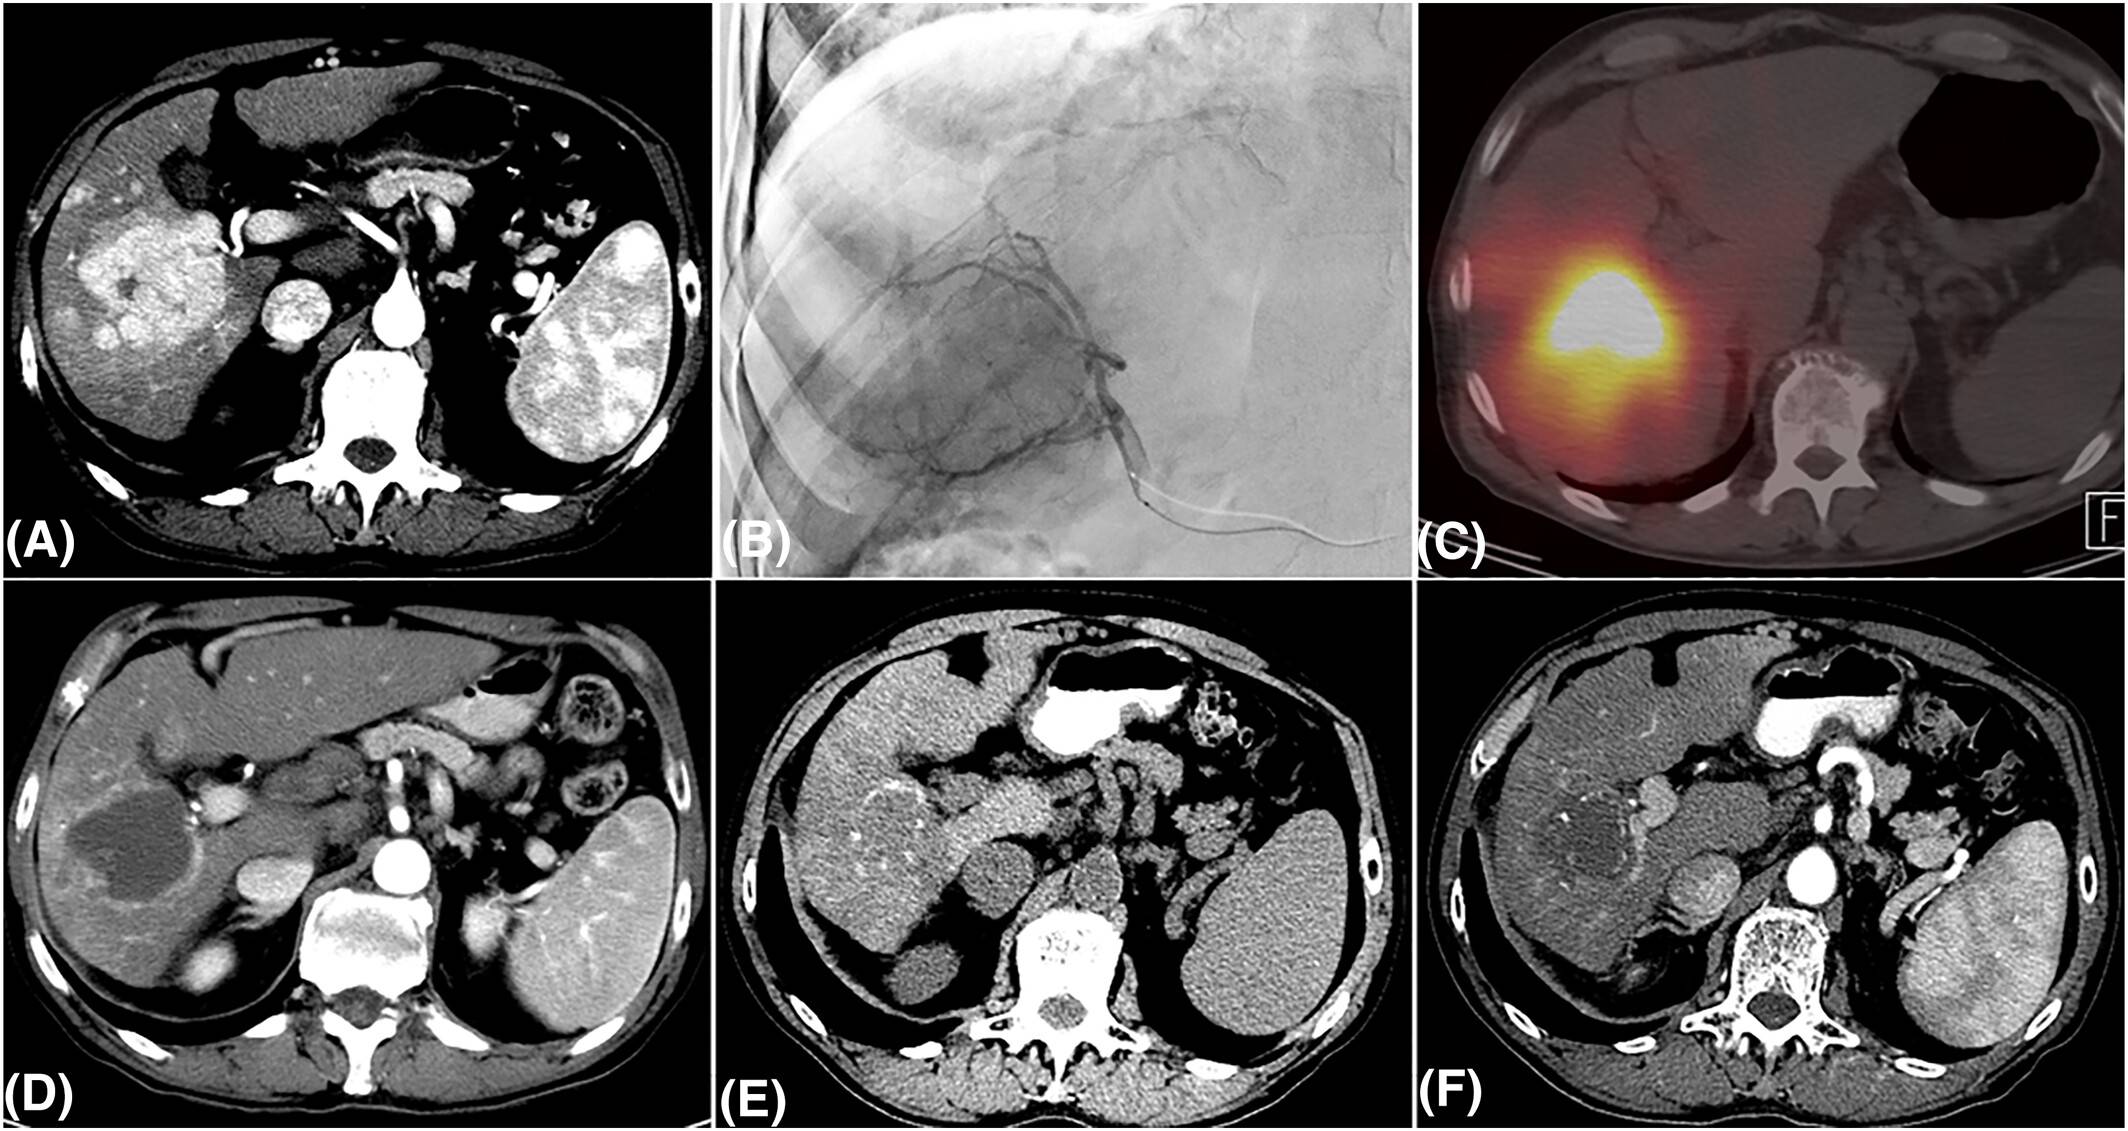

近期,多中心前瞻性Doorway临床试验已完成患者入组,该研究评估了钇-90(90Y)放射性栓塞在BCLC 0-B期HCC患者中的疗效,其结果预计将在未来数月公布,有望以前瞻性、独立的方式验证LEGACY研究的发现。图1为一例接受选择性⁹⁰Y治疗的HCC患者在2年随访中维持完全缓解的影像。

总体而言,经皮热消融(TA)是小肝癌患者一种安全且有效的治疗选择。不断增加的循证医学证据支持其疗效,使其在经过合理筛选的患者中被确立为一种具有根治潜力的替代方案。对于较大的肿瘤,结合先进剂量学评估实施的TARE可实现优异的局部肿瘤控制,相较TACE可改善OS,并在部分患者中具有潜在的根治性。图2展示了不同HCC临床场景下推荐的局部区域治疗策略。